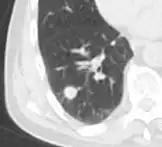

- Pleural retraction is far more common in cancers.[9] It is the pulling of visceral pleura towards the nodule.[9]

- Nodule with pleural retraction.[9]

- In this case, pleural retraction is seen as a triangular fat component.[9]